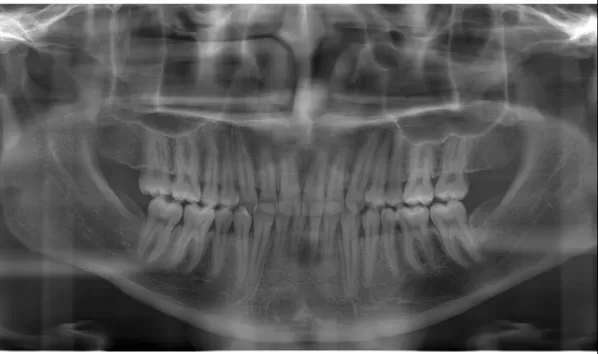

X-rays before treatment

[Panoramic Radiography/Lateral Cephalogram]